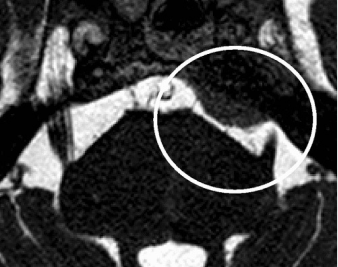

Though primarily a clinical diagnosis, Magnetic resonance imaging (MRI) imaging can detect changes in trigeminal root, any neuromuscular compression and to rule out secondary pathology. MRI can diagnose entire course of nerve, root atrophy, and CPA cistern. 3D fast imaging employing steady-state acquisition(FIESTA) and contrast-enhanced 3D time-of-flight (TOF) magnetic resonance angiography (MRA) in combination with unenhanced MRA are becoming popular in detecting the vessel involved and in detecting the vascular conflict.

Dandy proposed as early as 1930 that conservatively speaking the cause behind 30% of the patients a licted with Trigeminal Neuralgia was due to compression of the trigeminal nerve by a blood vessel. As of today the consensus behind the etiology of Classical Trigeminal Neuralgia is either compression or morphological changes in the trigeminal nerve brought about usually an artery in the cerebellopontine cistern. This is termed as ‘NEUROVASCULAR CONFLICT’ with compression. Transition of Schwann cell myelination to oligodendroglia myelination was observed in many anatomical specimens.

Evidence in recent times is in favor of a neuromuscular conflict characterized by neurovascular conflict involving morphological changes of distortion, distension, indentation, dislocation , flattening or atrophy of the trigeminal nerve is a hallmark feature of up to half the patients suffering from Classical Trigeminal Neuralgia. Conversely, there is a line of thought whether ‘simple contact’ between structures might play a role in the etiology.